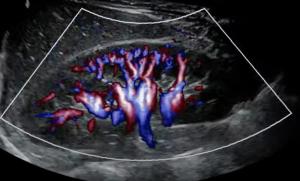

Mindray Debuts Resona A20 Premium Ultrasound Device at RSNA

Combining AI advances and ergonomic innovation, the R20 ultrasound platform reportedly offers a variety of automated tools and design features to facilitate a smoother, efficient imaging workflow.